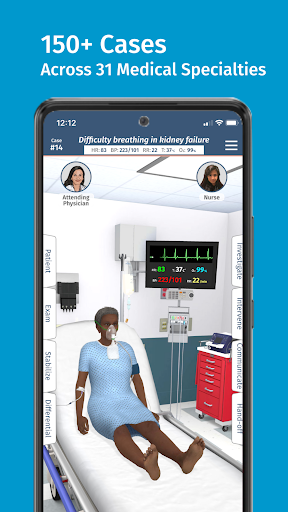

• Hơn 30 chuyên khoa chẩn đoán, bao gồm Y học cấp cứu, Sản phụ khoa và Nhi khoa

• Hơn 20 hình đại diện thực tế, bao gồm bệnh nhi và người lớn

Mỗi trường hợp đều là một thách thức mới trong Full Code: từ chẩn đoán thông thường đến các bệnh hiếm gặp. Bạn không chỉ giới hạn ở bệnh viện—Full Code đã mở rộng sang nội dung trước khi nhập viện và EMS. Ra khỏi khoa cấp cứu và vào xe cứu thương để ứng phó với mọi tình huống mới!